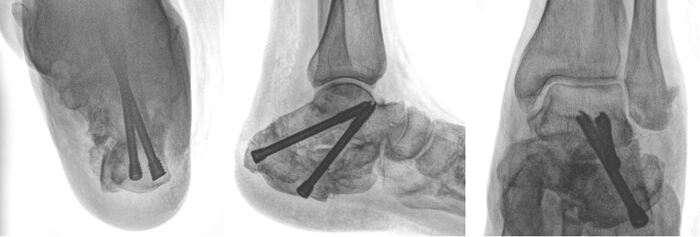

Коррекция деформаций малых пальцев стопы

Сегодня разберем ревизионный случай hallux valgus. И остановлюсь конкретно на малых пальцах (о ревизии первого луча опишу как-нибудь другой раз).

После реконструкции первого луча (в данном случае была выполнена остеотомия Austin, потому что позволяло состояние кости) мы получаем наличие деформации малых пальцев во фронтальной плоскости.

Важно изменить центр ротации второго и четвертого пальца, т.е. поднять головки малых лучей. С этой целью мной была выполнена чрескожная диафизарная остеотомия соответствующих плюсневых костей и чрескожная удлинняющая тенотомия длинных разгибателей второго и четвертого пальца при помощи иглы 18G.

Результаты рентгенографии, по которым видим, что анатомия пяточной кости восстановлена к максимально нативной. Также устранён субфибурялрный импиджмент синдром. Положение металлоконструкции правильнон.